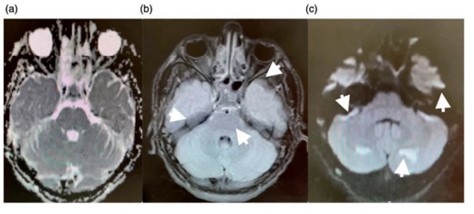

En esta investigación que se viene señalando, se puede mencionar el caso de un joven de 16 años, con alteración aguda del estado mental por inhalación de vapor de heroína. Se le efectuó una RM que evidenció hiperintensidades en T2 de la sustancia blanca simétrica difusa infratentorial y supratentorial. El diagnóstico clínico en este caso fue rabdomiólisis, que afecta predominantemente la musculatura posterior del cuello(21) (ver Imágenes 11 y 12).

Otro caso que merece ser comentado es el de un adolescente de 15 años que presentó encefalopatía y signos extrapiramidales por ingestión de metadona. La RM evidenció focos de infartos agudos en el caudado y putamen, así como infartos corticales de la línea divisoria de aguas parietales(21) (ver Imagen 13).